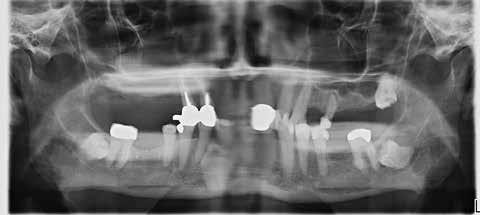

Fig. 1. Oversigt over udvælgelse af studiets kohorte.

Forkortelser: Antiresorptiv behandling (AR), Lavdosis antiresorptiv behandling (LDAR), Adjuverende antiresorptiv behandling (ADAR), Højdosis antiresorptiv behandling (HDAR), Medicinrelateret osteonekrose i kæberne (MRONJ).

Fig. 1. Overview of the study cohort selection.

Abbreviations: Antiresorptive therapy (AR), Low-dose antiresorptive therapy (LDAR), Adjuvant antiresorptive therapy (ADAR), High-dose antiresorptive therapy (HDAR), Drug-related osteonecrosis of the jaw (MRONJ).